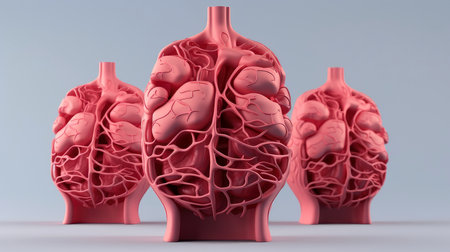

3D illustration mockup of the human organ system, Anatomy, Nervous, circulatory, digestive, excretory, urinary,and bone systems. Medical education concept, Generative AI illustration